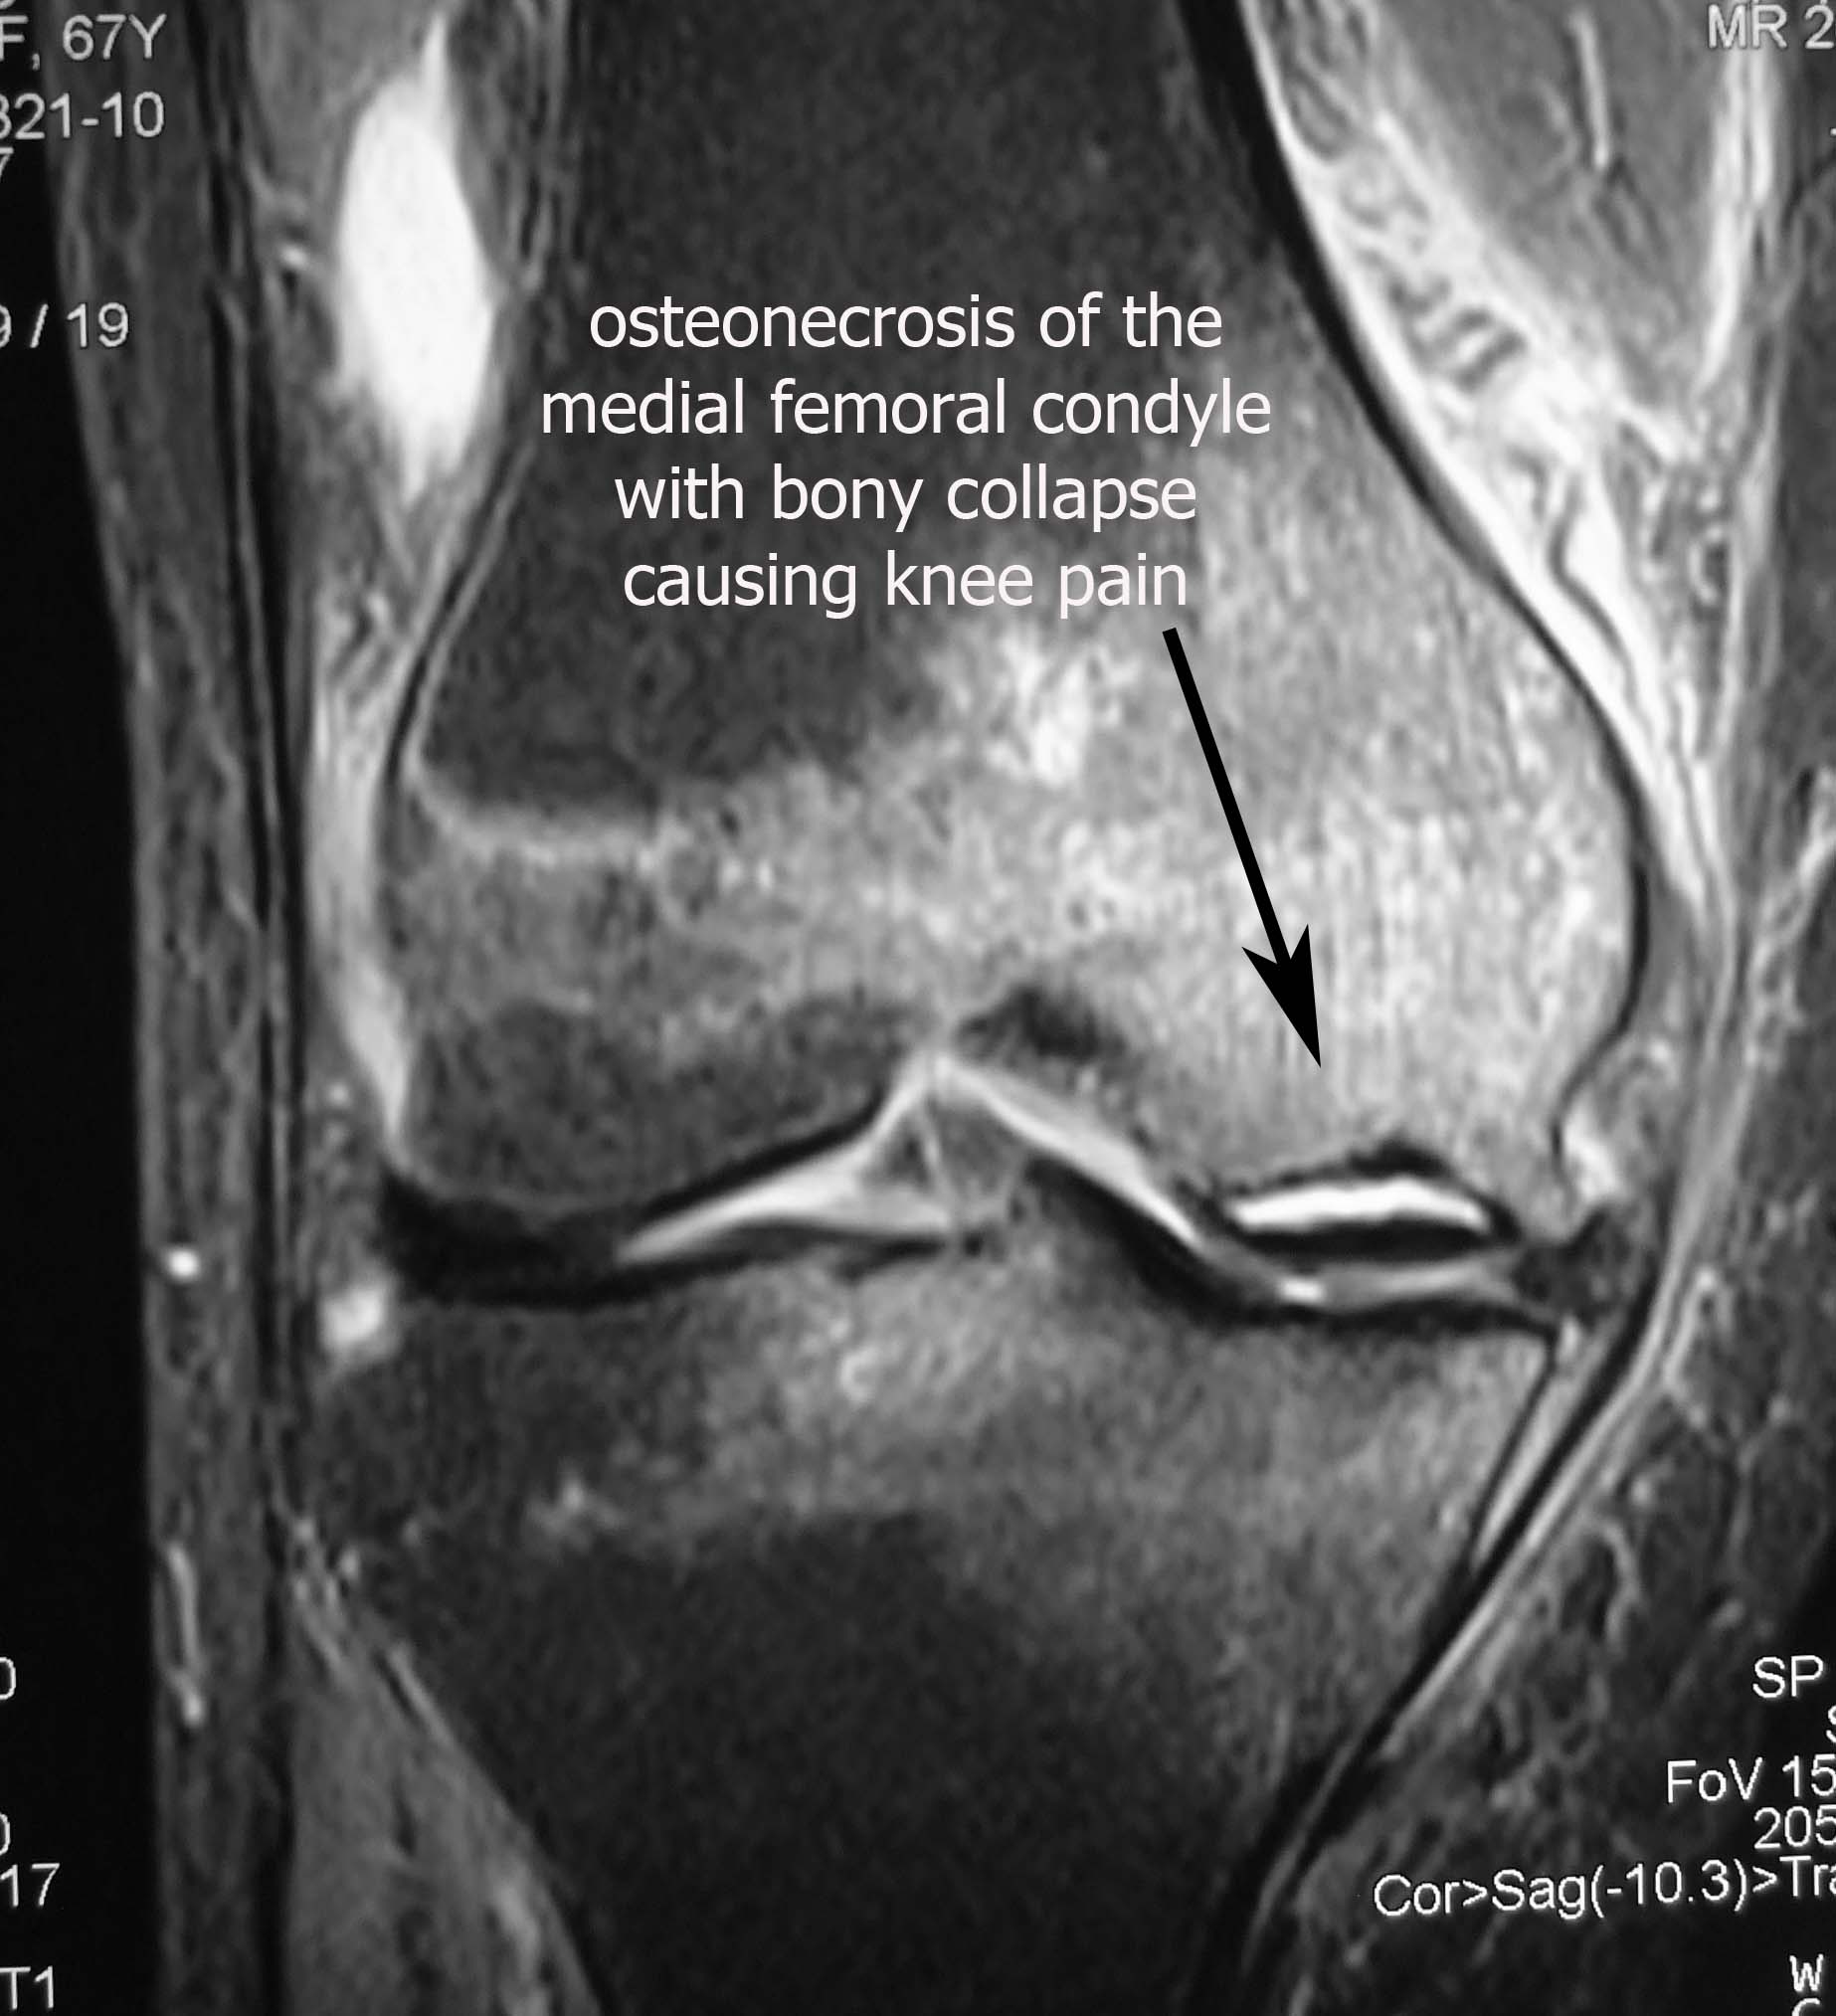

The x-rays showed flattening of the inner aspect of the knee (medial femoral condyle). This was consistent with a condition called osteonecrosis. This implied that the blood supply to that portion of the knee had been cut off leading to bone death. The dead bone flattened due to the pressure of walking.

This diagnosis was confirmed on MRI scan.